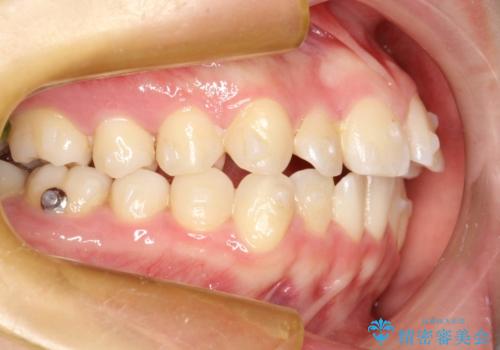

インビザラインによるガタつきの矯正治療 シンプル・短期間

- 20代女性

- invisalign full

- 1年6ヶ月

- 非抜歯、IPR+拡大によるマウスピース矯正を計画した。